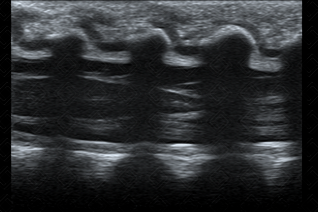

Texto alternativo para a imagem Figura 2. Créditos: Dra. Elazir Mota - Rio de Janeiro/RJ

Descrição das figuras 2 e 3: Ultrassonografia da coluna lombar evidenciando cone medular, tópico (ao nível de L1-L2) (seta branca). [cms-watermark]